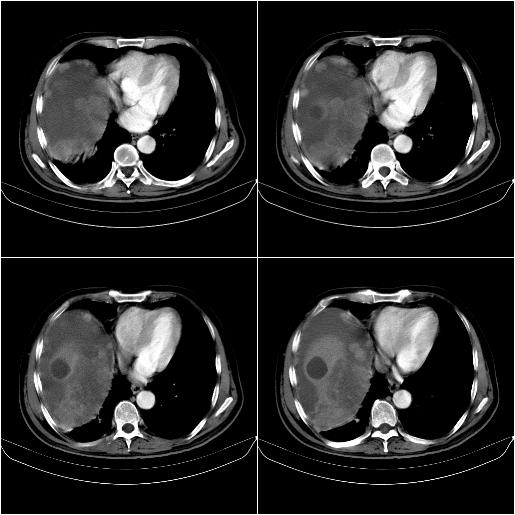

标题: CT21651:M,67Y,肝癌9月,介入术后3月。

m,67y,肝癌9月,介入术后3月。现腹胀、纳差、腹泻。

门静脉有很大的瘤栓,膈肌及膜膜有转移,不用再做了.

1)肝癌介入治疗术后碘油沉积不良。2)门静脉瘤栓形成,腹膜广泛性转移。3)肝硬化,脾大,腹水。4)慢性胆囊炎。